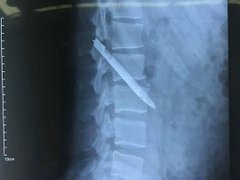

Lưỡi dao dài 13 cm nằm trong cơ thể chiến sĩ công an suốt 11 năm

Xã hội - 21/04/2018 15:00

Khi bệnh nhân là một chiến sĩ công an nhập viện với triệu chứng đau ở lưng, các bác sĩ đã khám, chụp X quang...